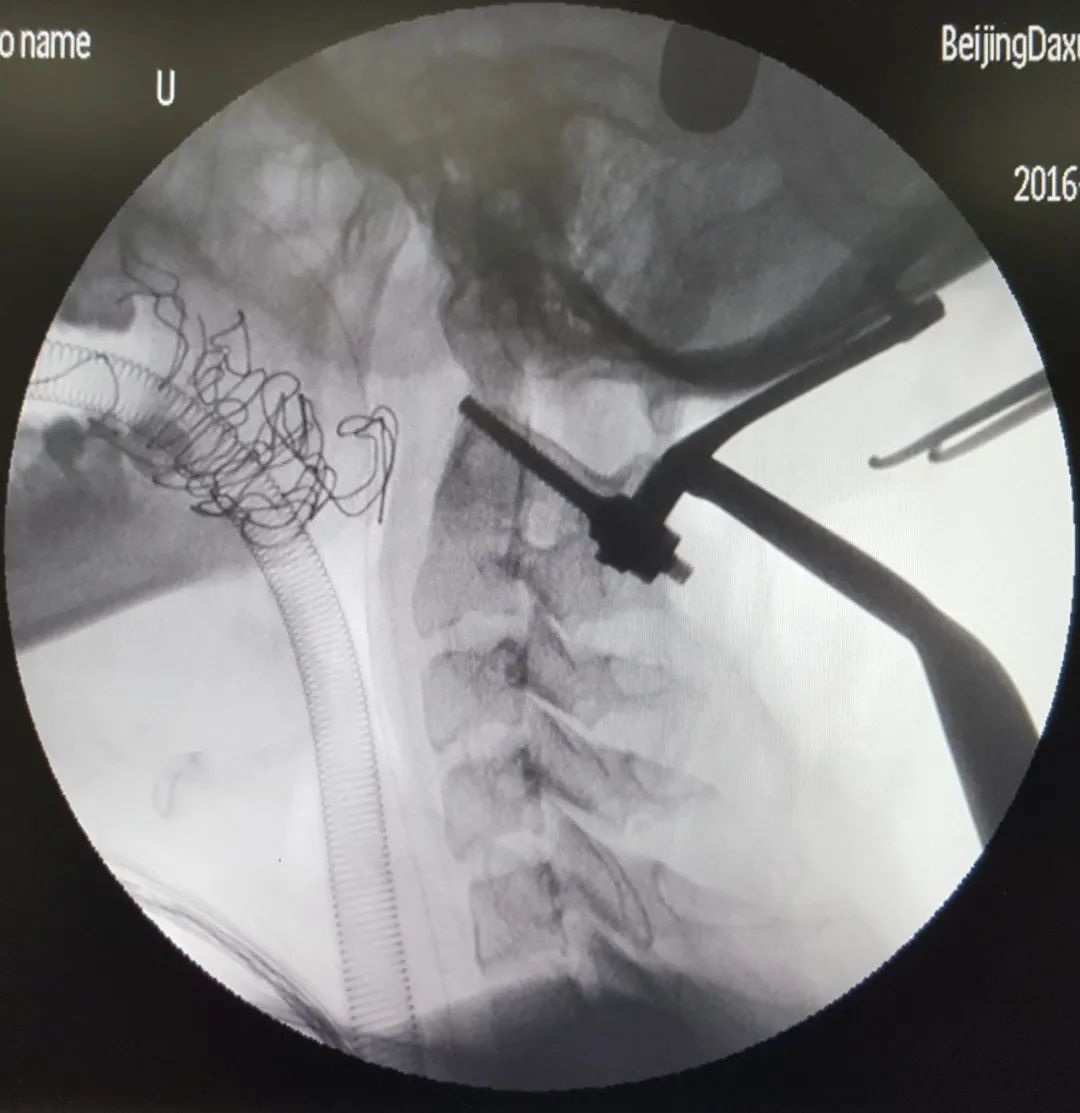

术中造影判断钉道是否合适

术中总会碰到吃不准钉道有没有穿透内壁的情况。确定方法有术中透视、电刀碰触试探、电生理监护、打开椎管直接探查等等。还有没有其他手段?——有的,用造影剂灌注钉道。